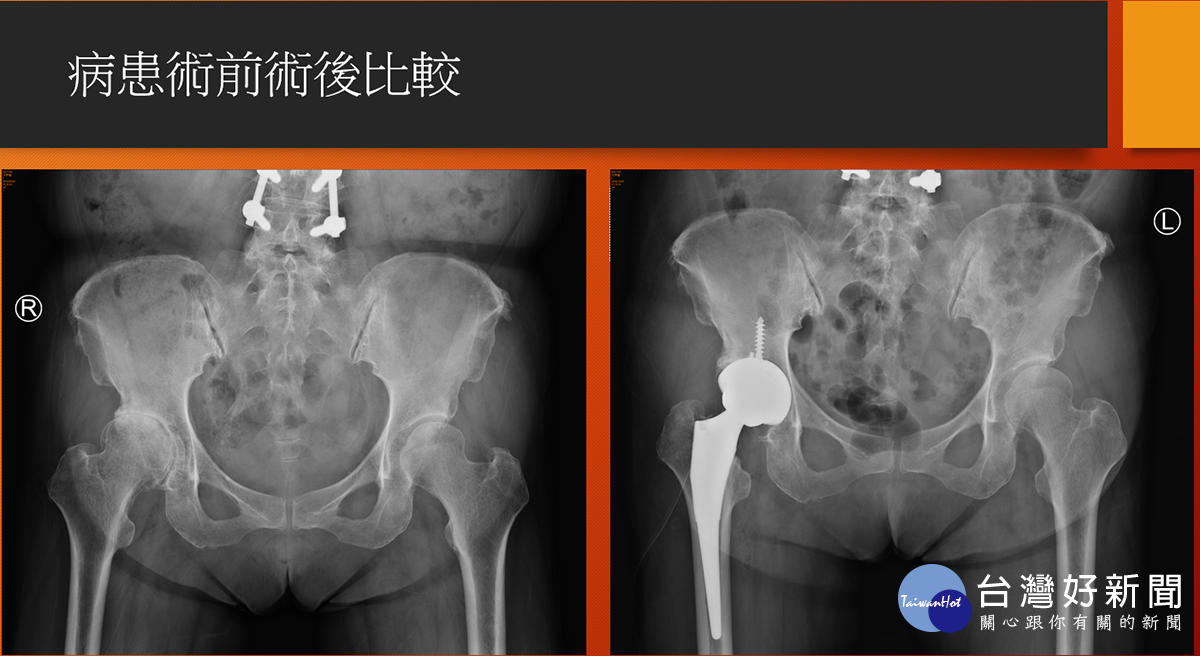

病人術前術後X光比較。(圖/七賢脊椎外科醫院提供)

高雄市一名63歲謝姓婦女在20多年前一場車禍, 造成右腳無法出力,中間歷經中醫針灸、骨傷、復健治療, 但因美髮師工作得長期站立,依靠左腳出力支撐, 卻又讓左腳開始產生疼痛, 直至去年底才在骨科門診中發現雙邊髖關節都已磨損嚴重, 醫師建議以“正前開”髖部手術,先處理持續疼痛感的左邊髖關節, 術後謝女士表示幾乎沒有疼痛感, 並在今年又另安排右邊髖關節置換手術, 順利解決謝女士多年的髖部疼痛不適。

七賢脊椎外科醫院骨關節科副院長楊華偉醫師說明, 一般在面臨人工髖節置換手術後的病人常遇到有疼痛、長短腳、 脫臼、復原時間較長等問題,但若是以正前開手術都可克服, 只是醫師在手術困難度上相對提高, 過去在國外文獻上統計之病人術後效果也非常良好, 目前在本院之案例也已達50人, 追蹤病人對於術後反應均以正面回饋。

楊華偉強調,正前開陶瓷人工髖關節手術, 其中陶瓷可解決磨損與腐蝕問題,也大幅降低二次開刀機會, 另外正前開之先進手術更能進一步改善常見術後之疼痛與復原時間問 題。而正前開手術對於嚴重骨鬆與體重過重BMI大於40的病人較 不適合,目前針對正前開之手術費用是健保給付範圍內, 除置換之髖關節自費材料外,不需有其他額外手術費用負擔。 有任何髖關節治療問題定要找專業骨科醫師做諮詢, 以選擇最適合個人的治療方式。